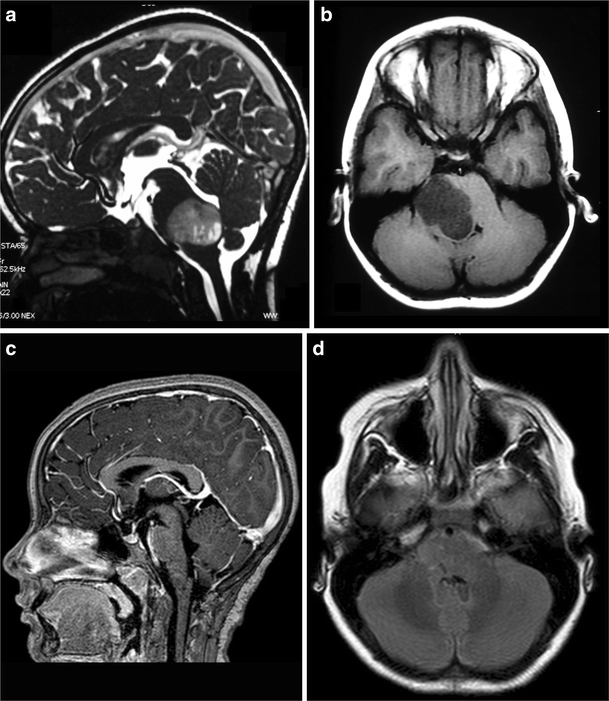

Fig. 4

figure 4

a, b 4-year-old girl admitted with a right Weber Syndrome with a solid/cystic anterior mesencephalic lesion with expansion towards the interpeduncular cistern. c, d 6-year follow-up showing total resection by fronto-orbito zygomatic approach (pilocytic astrocytoma)